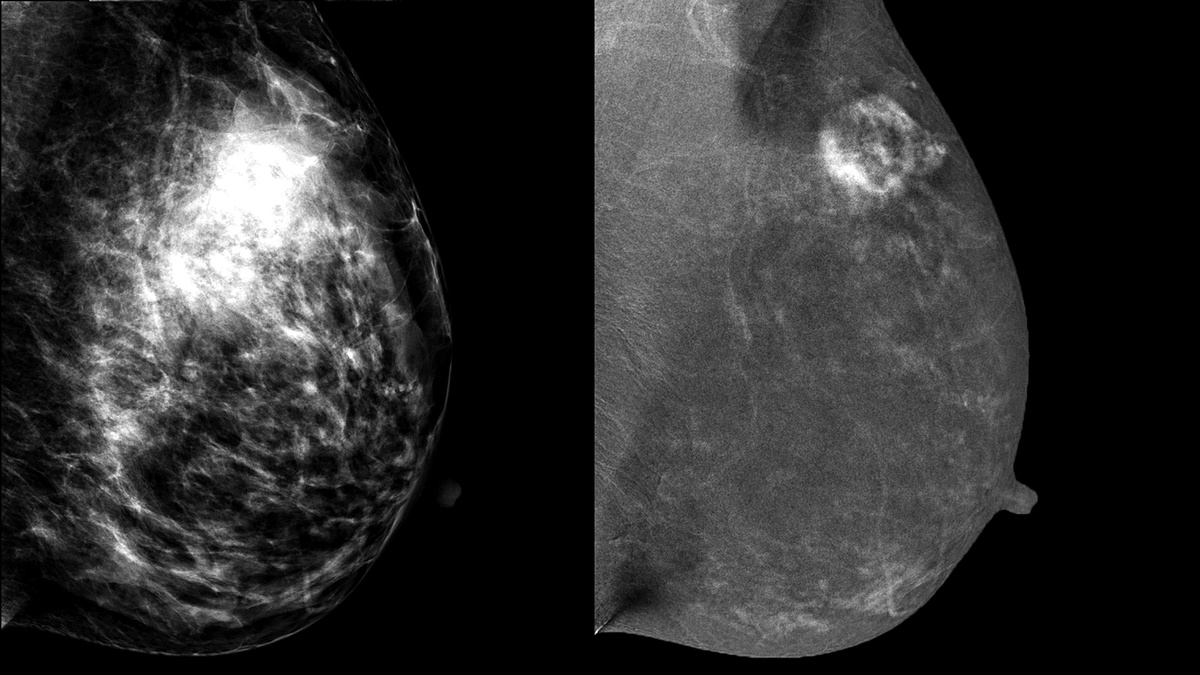

На низкоэнергетическом изображении (LM) не возникает свечения контраста, поэтому снимок схож с обычной - нативной маммографией. На высокоэнергетическом снимке (HM) становится видно контрастное вещество, накопленное в образованиях.

Двуэнергетическая контрастная маммография. Слева "низкоэнергитический" снимок (LM), с очень плотной железистой тканью в верхне-наружном квадранте. Справа объединенный снимок (REI), на котором четко видно образование с неровными толтыми контурами, участками усиления внутри образования. Впоследствии гистологически подтверждена инвазивная протоковая карцинома.